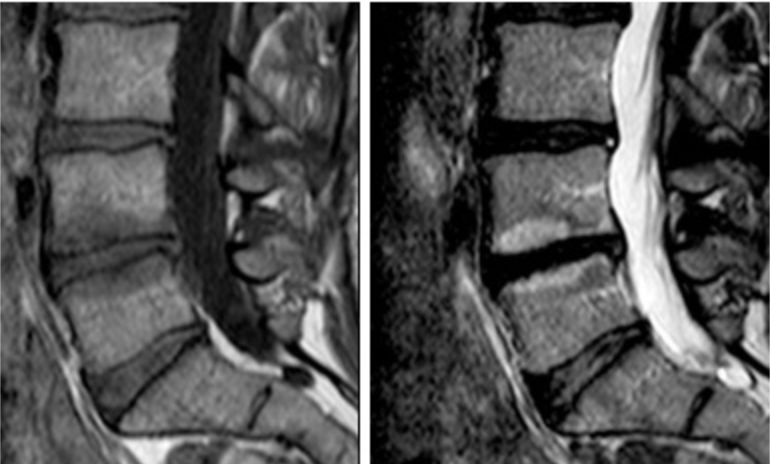

Изменение по типу modic 1

Изменение по типу modic 1 110 фотографий